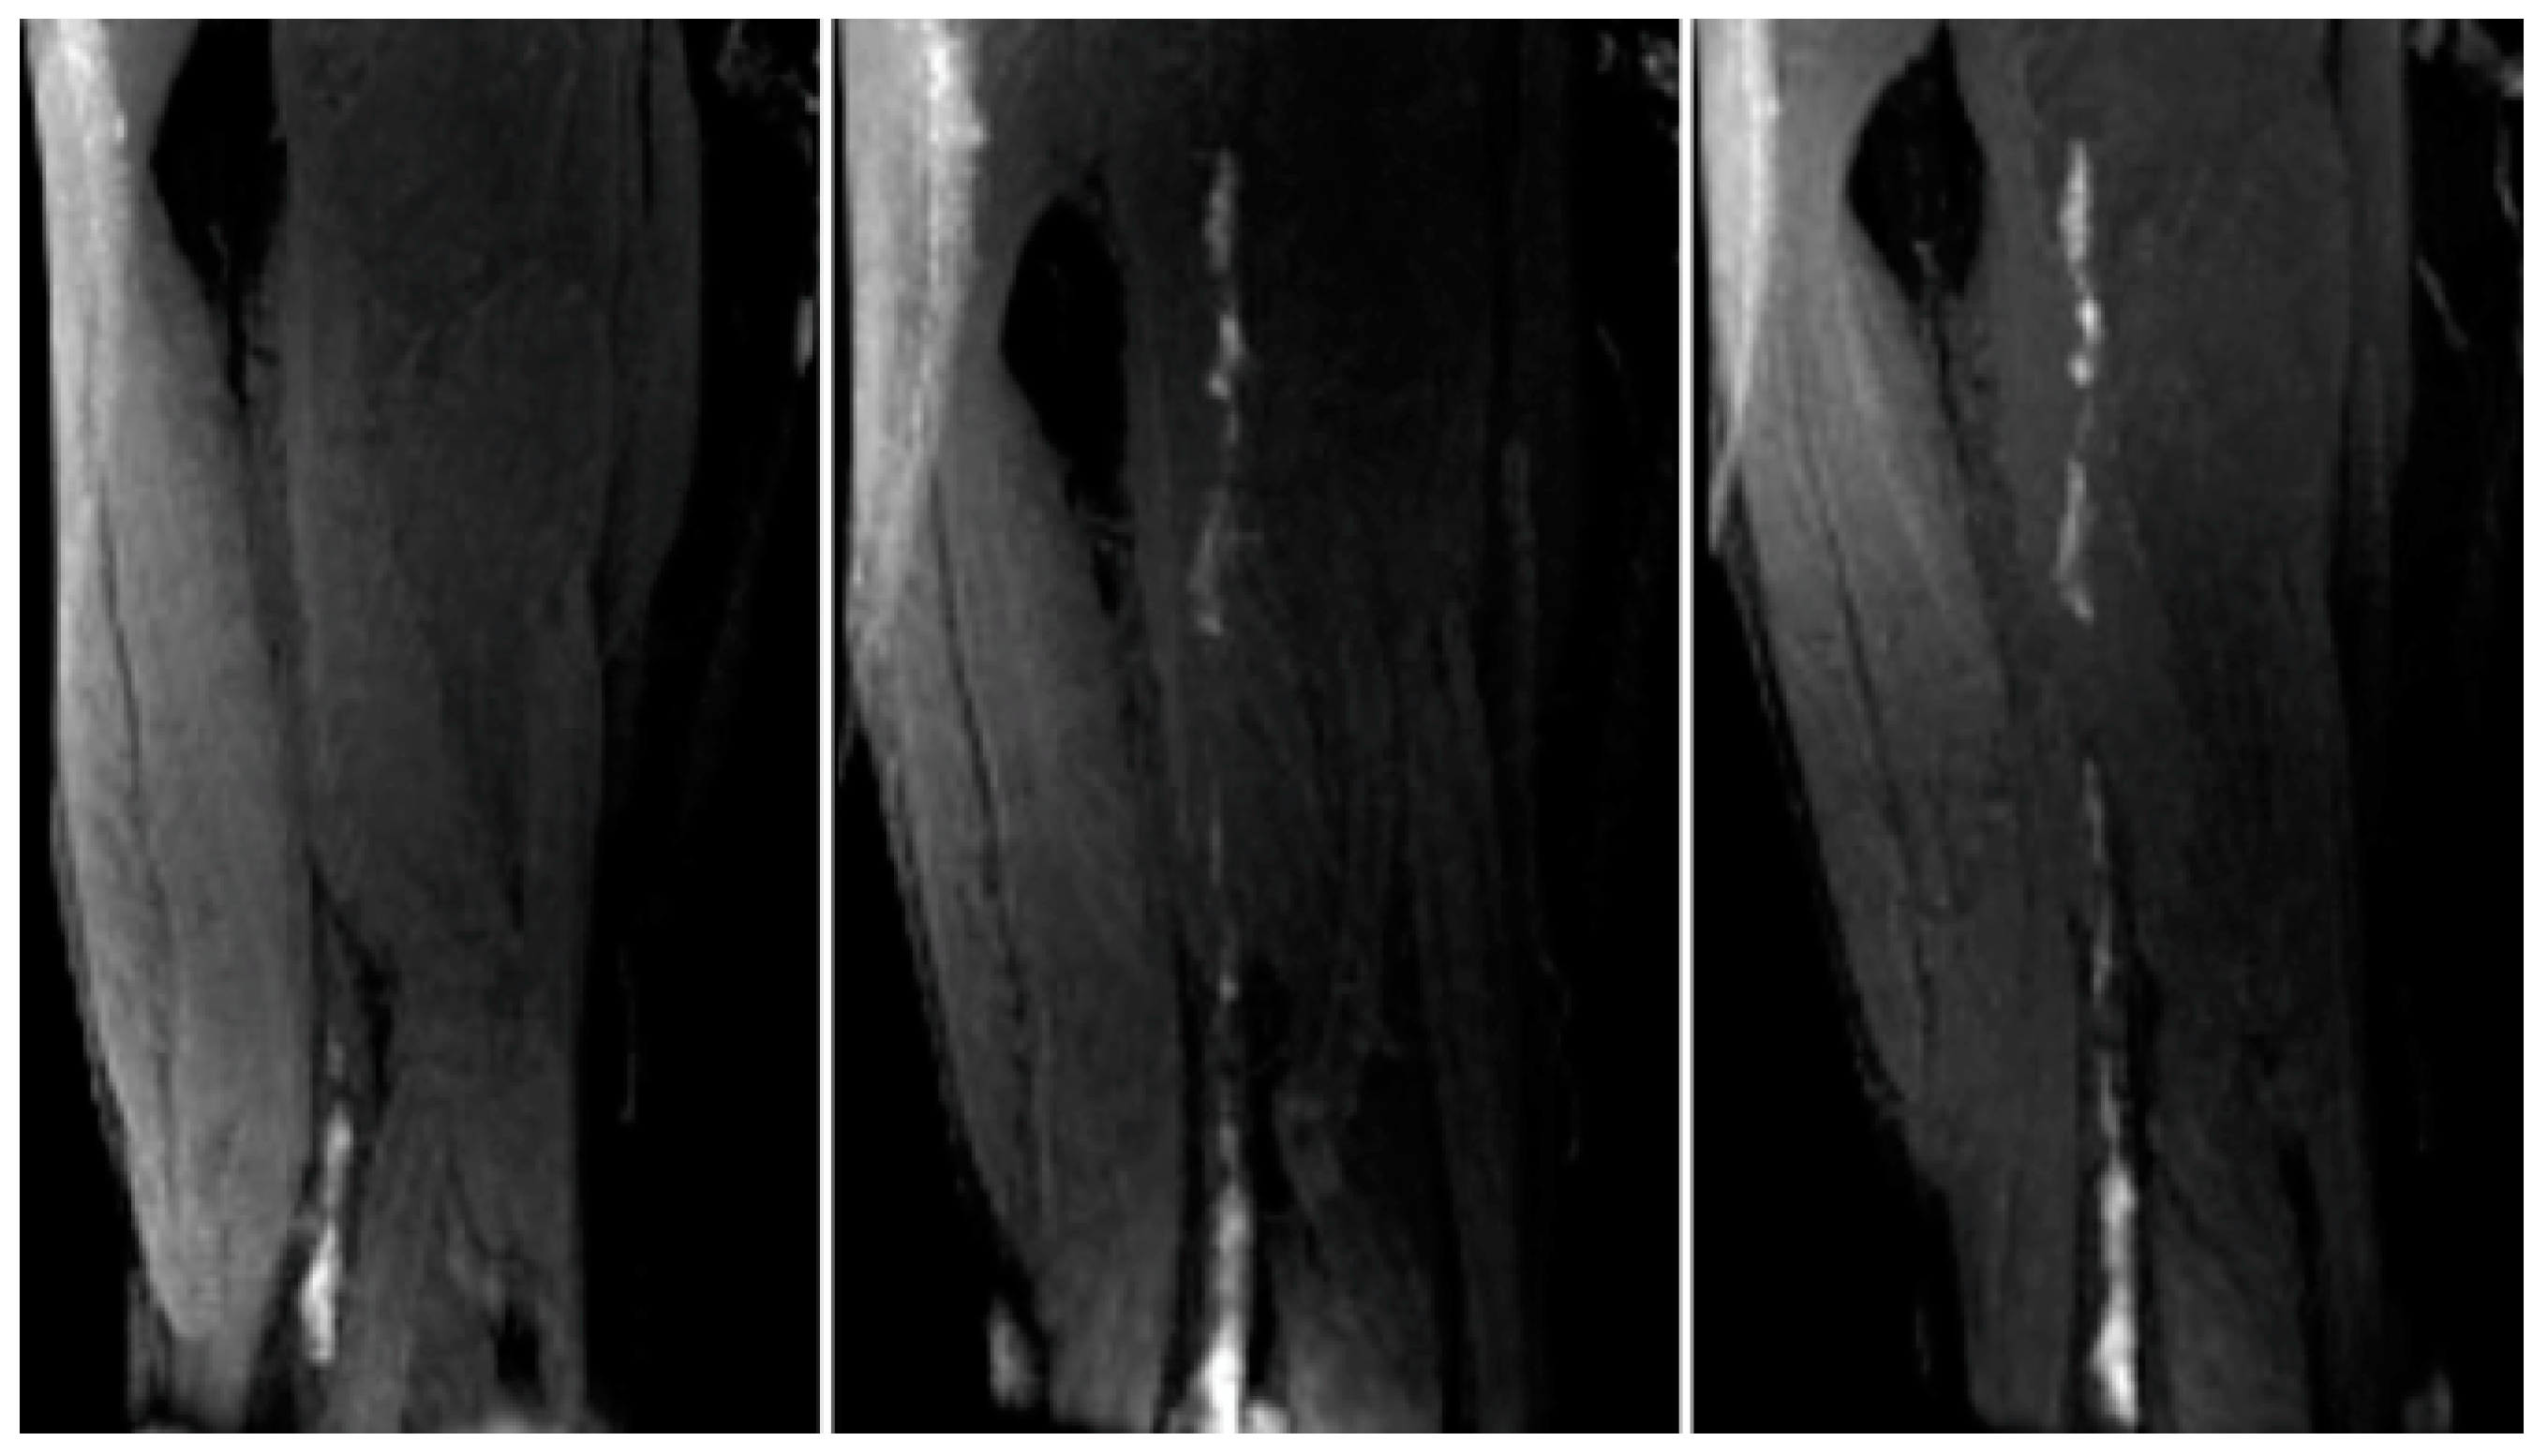

- Andia, M.E.; Saha, P.; Jenkins, J.; Modarai, B.; Wiethoff, A.J.; Phinikaridou, A.; Grover, S.P.; Patel, A.S.; Schaeffter, T.; Smith, A.; et al. Fibrin-Targeted Magnetic Resonance Imaging Allows In Vivo Quantification of Thrombus Fibrin Content and Identifies Thrombi Amenable for Thrombolysis. Arterioscler. Thromb. Vasc. Biol. 2014, 34, 1193–1198. [Google Scholar] [CrossRef]